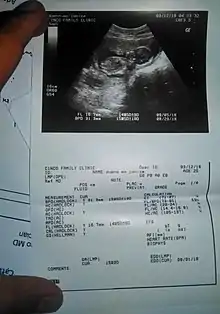

Gynecology and obstetrics

Gynecologic ultrasonography examines female pelvic organs (specifically the uterus, ovaries, and fallopian tubes) as well as the bladder, adnexa, and pouch of Douglas. It uses transducers designed for approaches through the lower abdominal wall, curvilinear and sector, and specialty transducers such as transvaginal ultrasound.[18]

Obstetrical sonography was originally developed in the late 1950s and 1960s by Sir Ian Donald[19][20] and is commonly used during pregnancy to check the development and presentation of the fetus. It can be used to identify many conditions that could be potentially harmful to the mother and/or baby possibly remaining undiagnosed or with delayed diagnosis in the absence of sonography. It is currently believed that the risk of delayed diagnosis is greater than the small risk, if any, associated with undergoing an ultrasound scan. However, its use for non-medical purposes such as fetal "keepsake" videos and photos is discouraged.[21]

Obstetric ultrasound is primarily used to:

- Date the pregnancy (gestational age)

- Confirm fetal viability

- Determine location of fetus, intrauterine vs ectopic

- Check the location of the placenta in relation to the cervix

- Check for the number of fetuses (multiple pregnancy)

- Check for major physical abnormalities.

- Assess fetal growth (for evidence of intrauterine growth restriction (IUGR))

- Check for fetal movement and heartbeat.

- Determine the sex of the baby